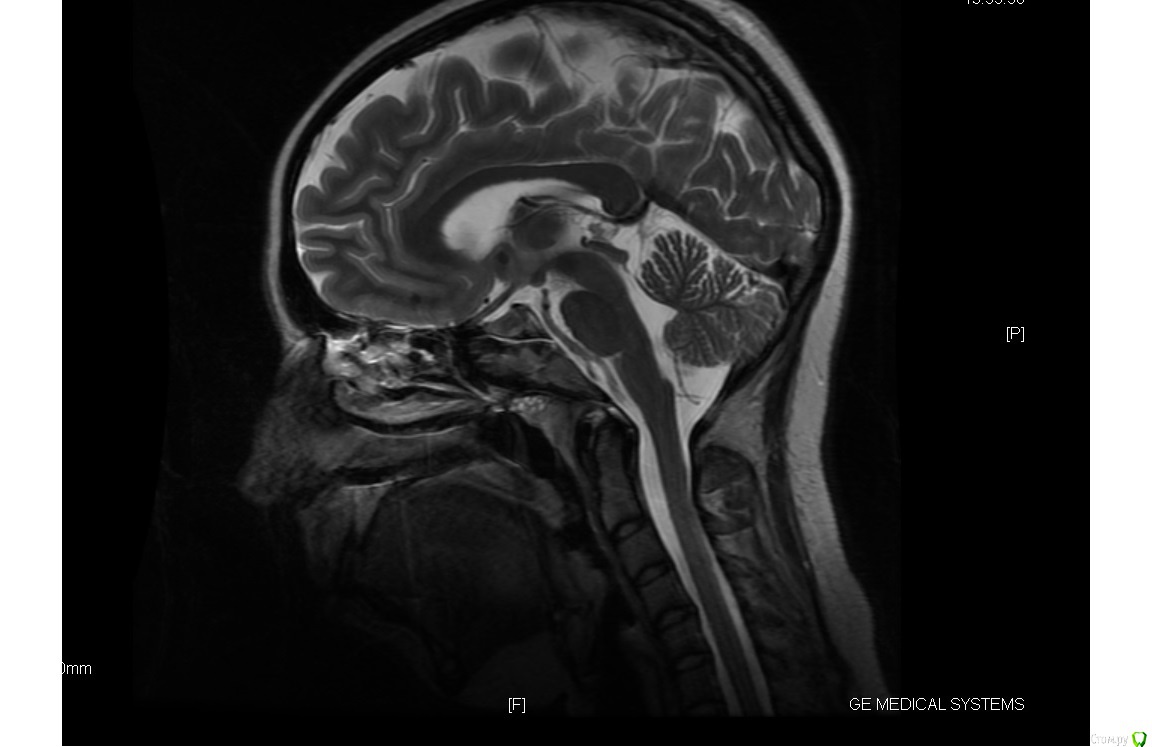

Chudo Опубликовано 14 октября, 2017 Поделиться Опубликовано 14 октября, 2017 Здравствуйте. Нужна консультация. Мне 30 лет, у меня остеопороз. 3 года после родов хожу лечить зубы как на работу (после родов состояние зубов плачевное, на панорамном снимке все видно). Сначала просто лечили кариес, удаляли нервы, ставили пломбы. У меня было две нижних 8 которые сильно сдавили мне все зубы. Мой врач все время говорила что надо ставить брекеты из-за неправильного прикуса, но денег и времени не было (маленький ребенок, отец инвалид 1 группы и муж в бесконечных командировках). В конце 2015 года я пошла удалять восьмерку, так как боль от давления на зубы стала нестерпимая. Располосовали щеку что бы поддеть 8 которая стояла горизонтально(снимок перед удалением 8 прилагаю). Зуб удаляли в Краевом клиническом стоматологическом центре Гбуз г. Краснодар. Заживало долго потому как в щеке остался осколок челюсти, месяц я ходила на перевязку и жаловалась на боль в щеке и на застрявшие нити от бинта который мне запихивали в лунку в десне, нити я вытаскивала дома сама потому что врачи их не видели, а я почему то да (никакой реакции со стороны врача не было. Я слышала только : это нормально, все пройдет). Через месяц у меня начала подниматься температура, а потом осколок из щеки стал выходить вместе с гноем из того места где мне резали щеку при удалении 8. В итоге спустя два месяца после этого удаления начался кошмар. У меня пошло воспаление по всей полости рта и верхние передние зубы начали расходиться. Все это время ходила лечила десны. Прижигала лазером воспаления в деснах, полоскала, мазала гелями, врачи все говорила что у меня просто организм подвержен постоянному воспалительному процессу и уммунитет у меня никакой . В начале 2017 дочка ударила меня затылком по нижним передним зубам, из-за чего 1 зубы стал шататься и на приему у своего зубного выяснилось, что у меня пародонтоз и что зуб у меня держится на одной только десне. Сделала мне шинирование шатающегося зуба с рекомендацией мазать гелем метрогил дента что бы десна пришла в себя и через месяц придти на прием и снять шинирование. Через месяц ситуация не улучшилась, шинирование оставили, продолжала ходить через 1-2 месяца на чистку зубов от камня и налета.В общем какая сейчас ситуация. В начале этого лета мне сказали что без брекетов я потеряю зубы, после нового снимка ортодонт сказала что брекеты она мне ставить не может из-за пародонтоза чуть ли не 3 степени и ужасного состояния моей челюсти и что зубы у меня выпадут из-за этого еще быстрее. Импланты мне сказали ставить просто некуда из-за малого количества челюстной кости. После 2 месяцев соображений ортодонт выдвинули вердикт ставить мне брекеты на мой страх и риск, если зубы выпадут, будут делать какие то протезы которые будут крепиться к боковым зубам. Ответа внятного почему мне за все это время не предлагали адекватного лечения пародонтоза я не услышала, теперь есть то, что есть ...Вот у меня к Вам дорогие специалисты 2 вопроса 1. Какова вероятность выпадения зубов при брекетах в моем случае? Я знаю что обязательно нужно вычистить все пародонтальные карманы, снять воспаление и т.д. То есть меня интересует можно ли вообще теоретически поставить брекеты с такой ушатаной челюстной костью?2. И если брекеты ставить нельзя, то что вообще делать? P.S.: Еще лет в 17 - 18 было удалено по 5 с верхней челюсти с обеих сторон из-за воспаления надкостницы (удаляли не за раз, а с интервалом в год). Рентген снимка с боку не было, есть снимок МРТ, может быть хоть чуть чуть будет что-то на них видно Ссылка на комментарий